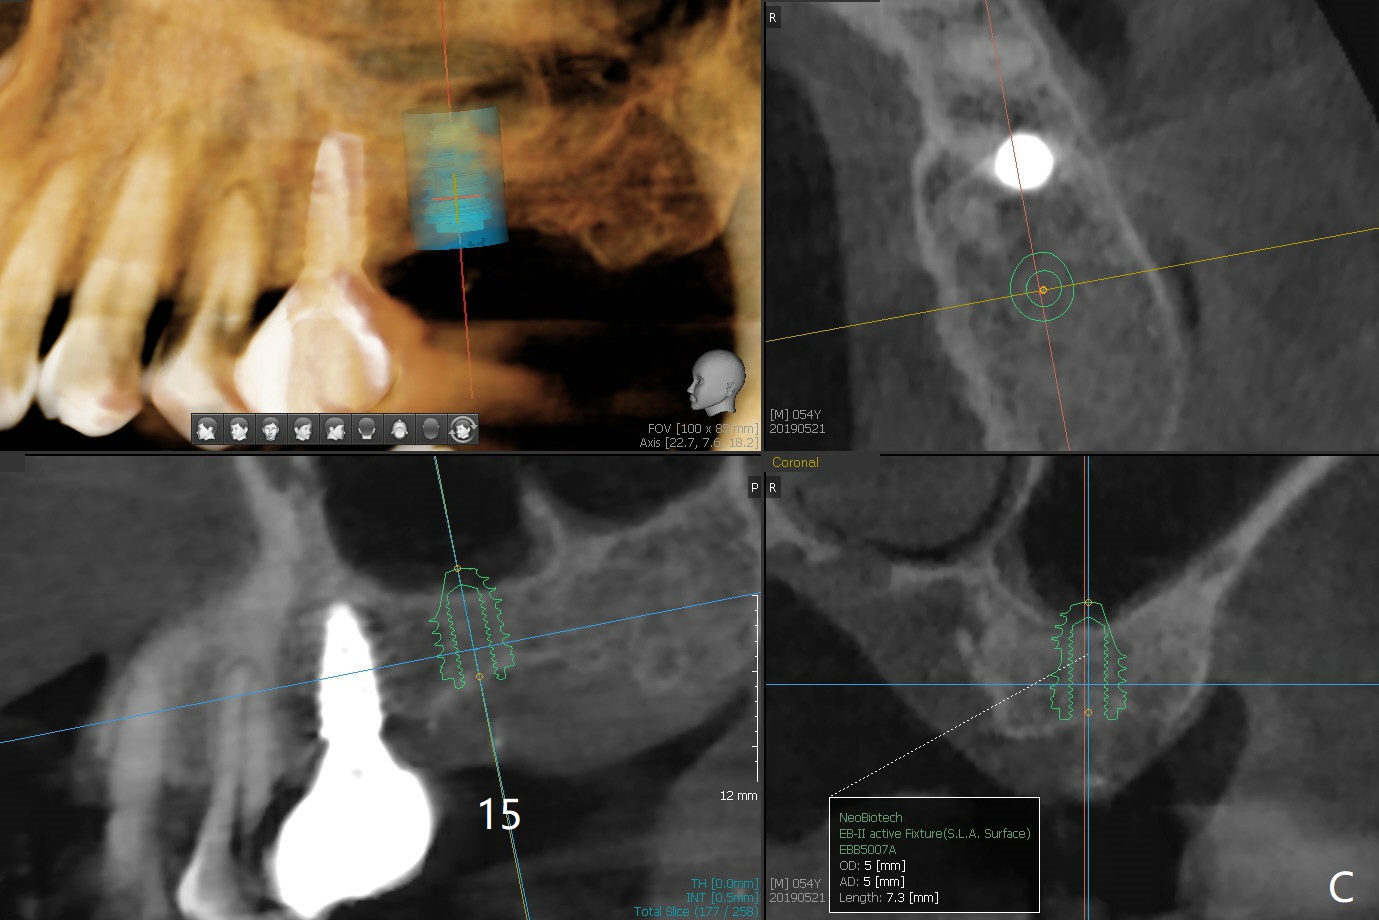

A 54-year-old man remains difficult in mastication in spite of implant placement at #14 and 31 (Fig. A, B, E, including screw loosening (poor trajectory at #14)). In addition to 2 more implants at #15 and 18 with guide, malocclusion seems to be necessary to be addressed (Fig.1-5). It appears that UR, LL4 should be extracted for orthodontic treatment (Fig.6-10). To reduce screw loosening, IS guide will be used to place IBS (5x9mm) and tissue-level (5x11mm) implants at #15 (PRF)and 18, respectively. If the one at #14 or 15 keeps loosening, splint #14 and 15 crowns. In fact the patient agrees with limited ortho (UR7 cross bite).